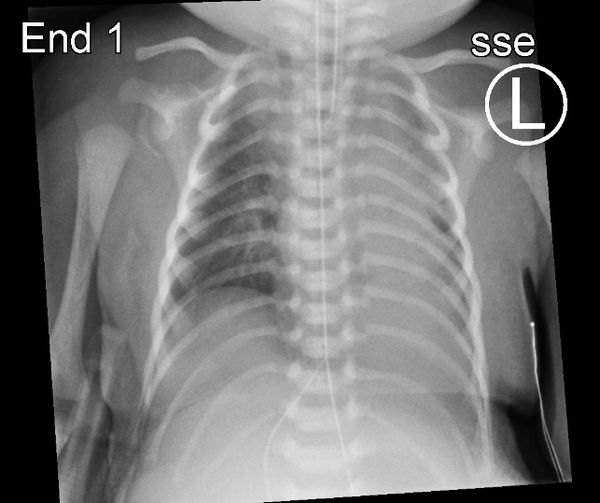

(Pic: chest x-ray demonstrating small lungs in a patient with a giant omphalocele)

The first step in management is neonatal resuscitation and stabilization, making sure the baby is able to breathe appropriately and the heart is functioning properly as these kids are often born with underdeveloped lungs (pulmonary hypoplasia) and may have an associated heart defect